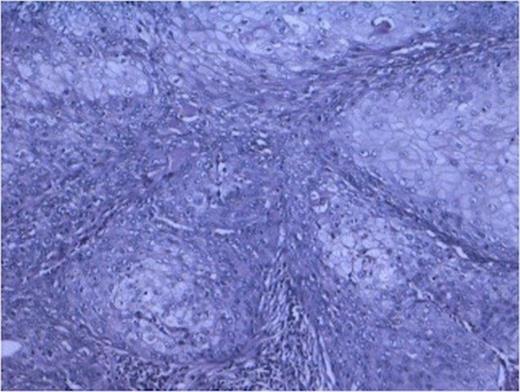

Histopathology from solid portions in pelvis region showed features of moderately differentiated squamous cell carcinoma (Fig 3). The tumor was not involving retroperitoneal soft tissue including renal vessels, Gerota’s fascia and lymph nodes.

DISCUSSION